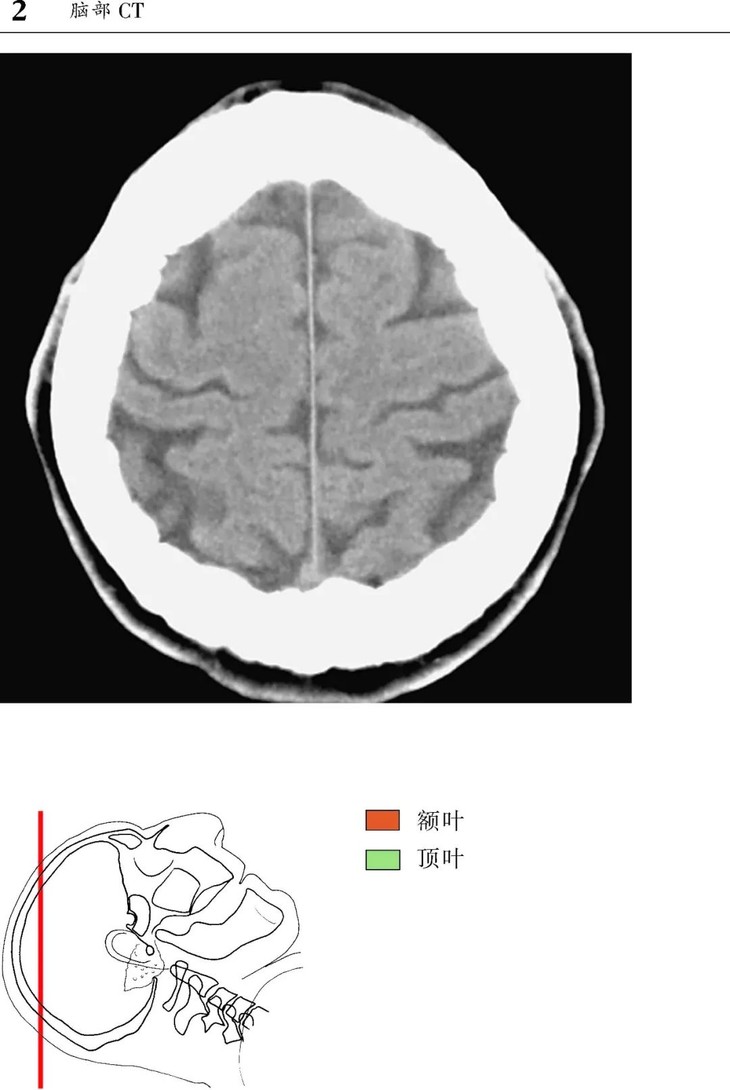

本书为断层解剖图谱,包括头颈部断层解剖,还包括脑部血管造影术,每一层面都包括精确的断层解剖和对应的彩色插图,左边页面为CT/MR图像,右边页面为对应的彩色手绘解剖示意图,便于学习和记忆!

1、版面采用教学式设计,2页为一个单元,左边页面为CT/MR图像,右边页面为对应的彩色手绘解剖示意图,并一一注明了解剖部位。

2、几百幅高清的CT/MR图片,对解剖结构显示更加清晰,其中许多图片都是采用最新的设备扫描的,如3.0T MRI,64层CT。

3、彩色手绘示意图中,各断层图像中同一个解剖结构均采用相同的颜色标注,便于识别。